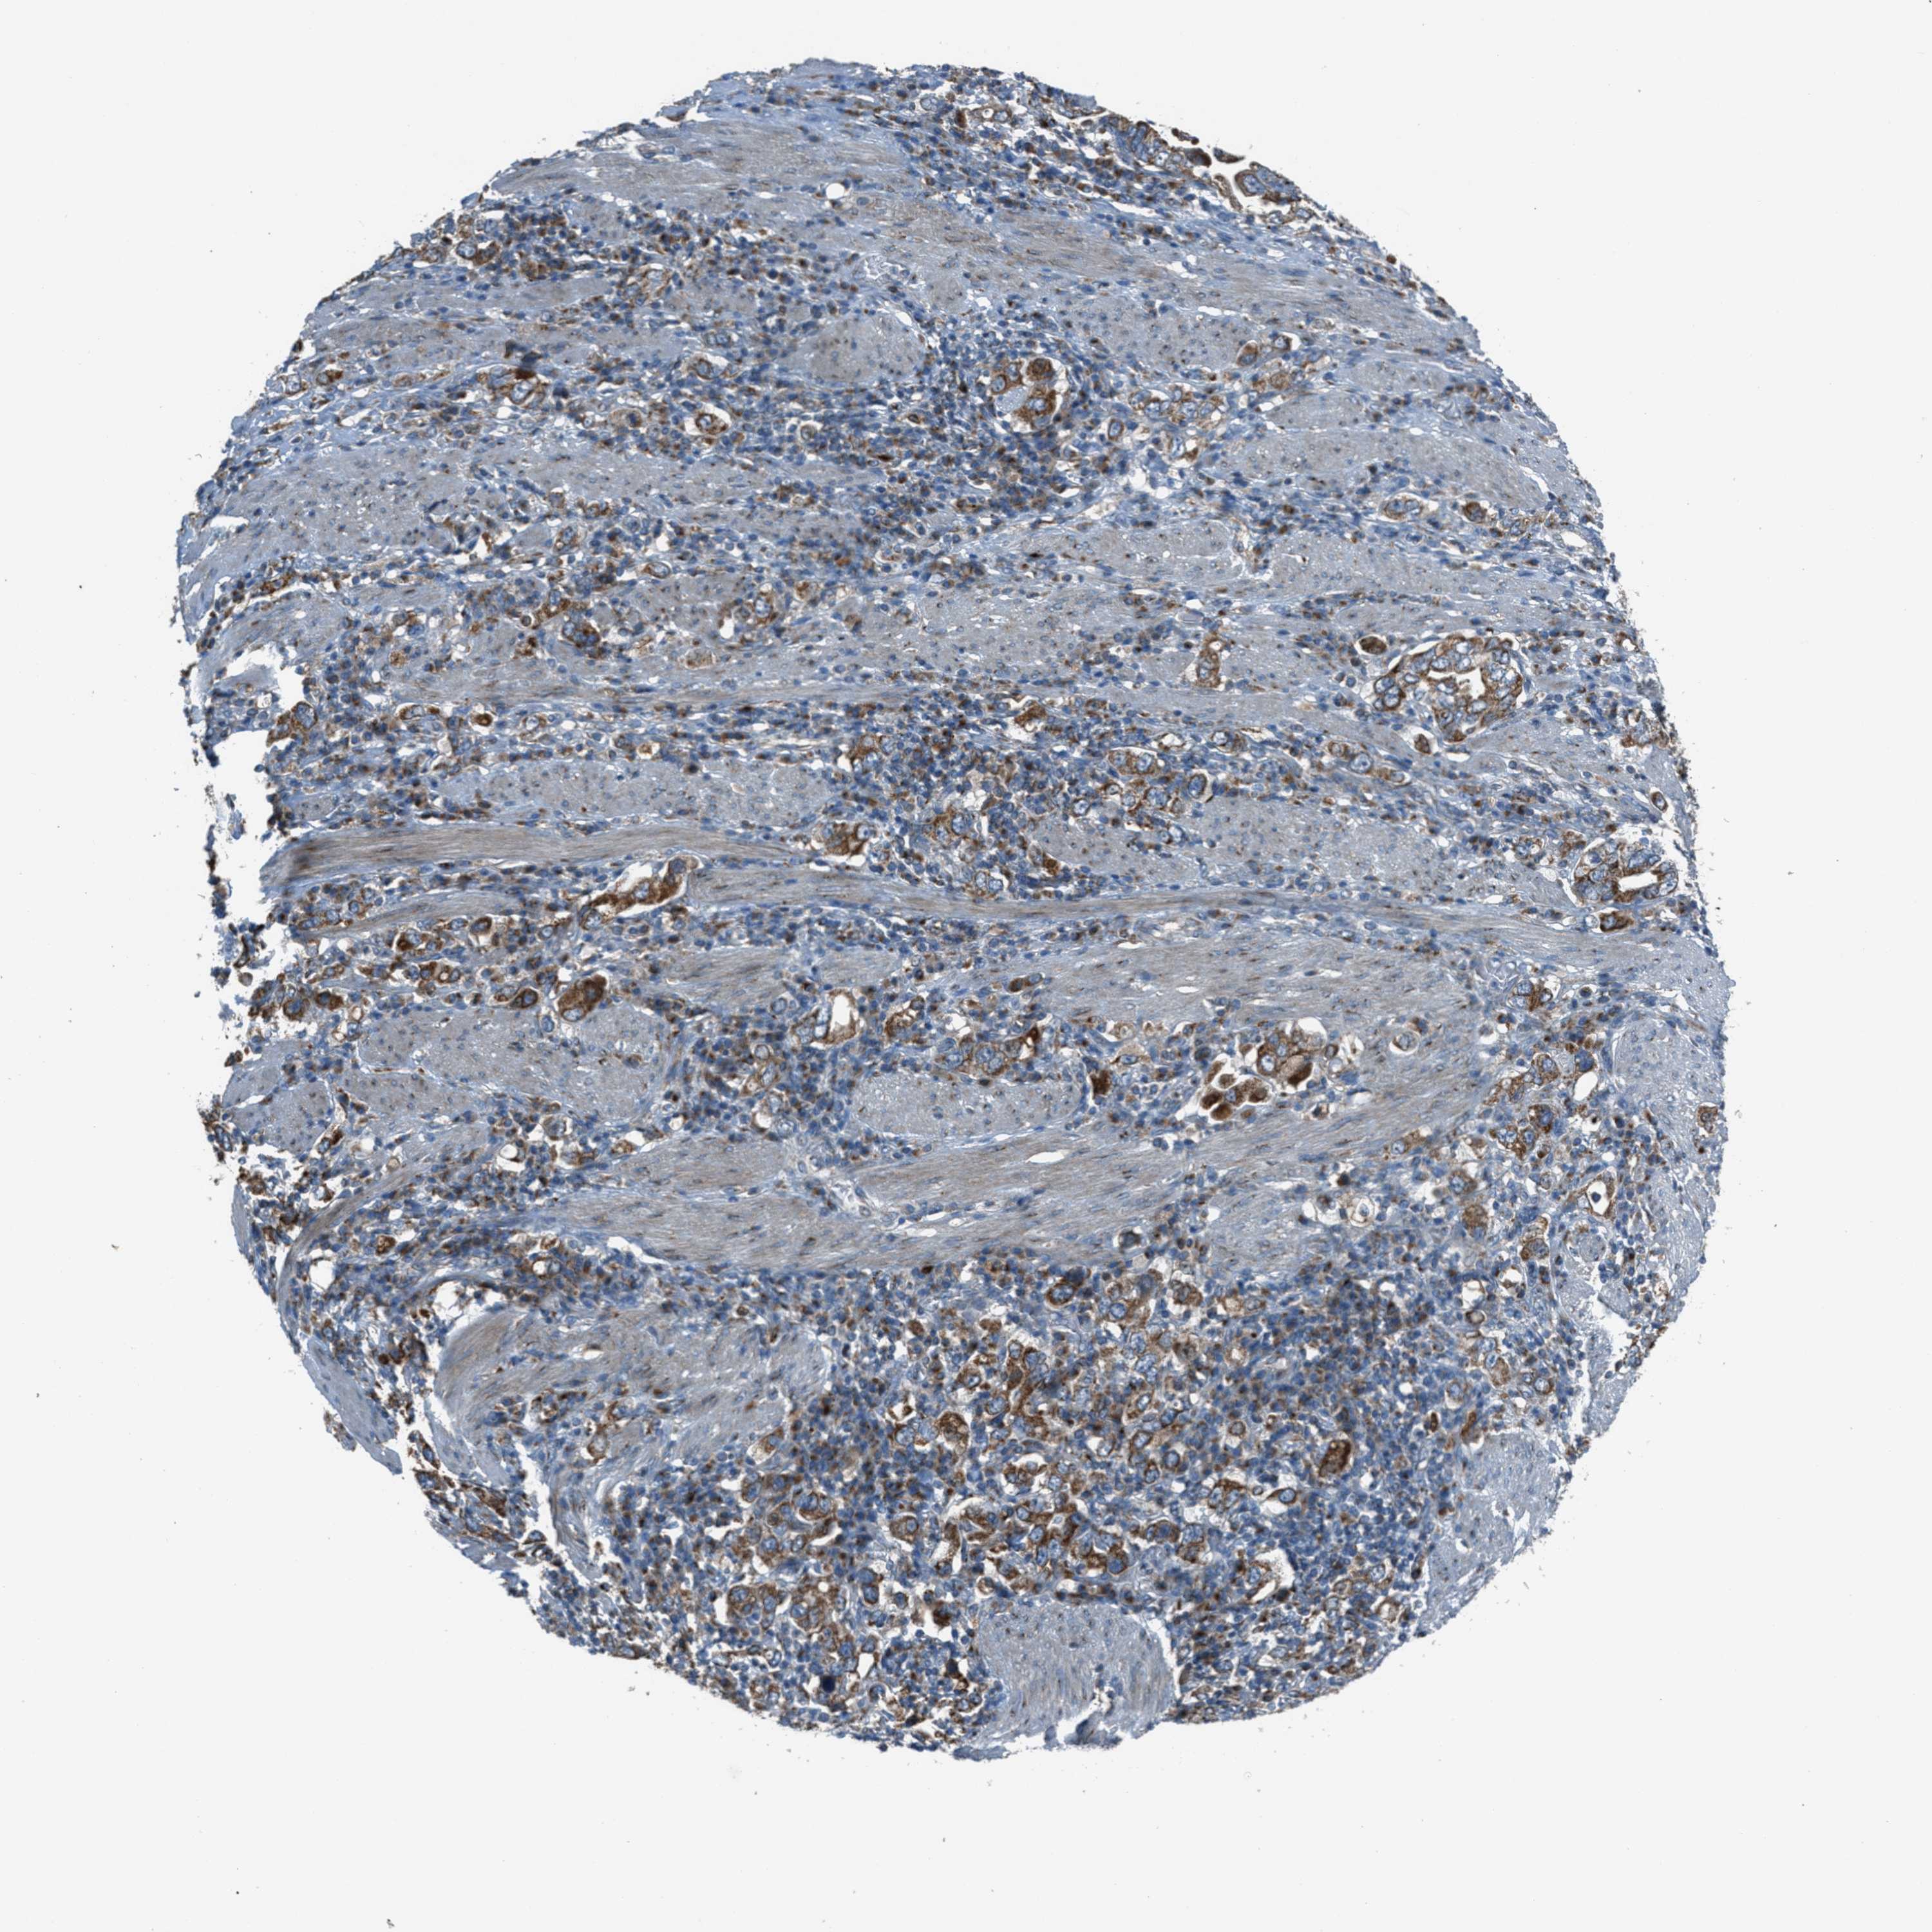

STOMACH CANCER - Protein expressioni

A mouse-over function shows sample information and annotation data. Click on an image to view it in a full screen mode. Samples can be filtered based on level of antibody staining by selecting one or several of the following categories: high, medium, low and not detected. The assay and annotation is described here.

Antibody stainingi

Antibody staining in the annotated cell types in the current human tissue is reported as not detected, low, medium, or high, based on conventional immunohistochemistry profiling in selected tissues. This score is based on the combination of the staining intensity and fraction of stained cells.

Each image is clickable and will lead to virtual microscopy that enables deeper exploration of all samples and also displays staining intensity scores, fraction scores and subcellular localization as well as patient and tissue information for each sample.

Antibody HPA017995

Staining

High

Medium

Low

Not detected

Intensity

Strong

Moderate

Weak

Negative

Quantity

>75%

75%-25%

<25%

None

Location

Nuclear

Cytoplasmic/membranous

Cytoplasmic/membranous,nuclear

Adenocarcinoma, NOS